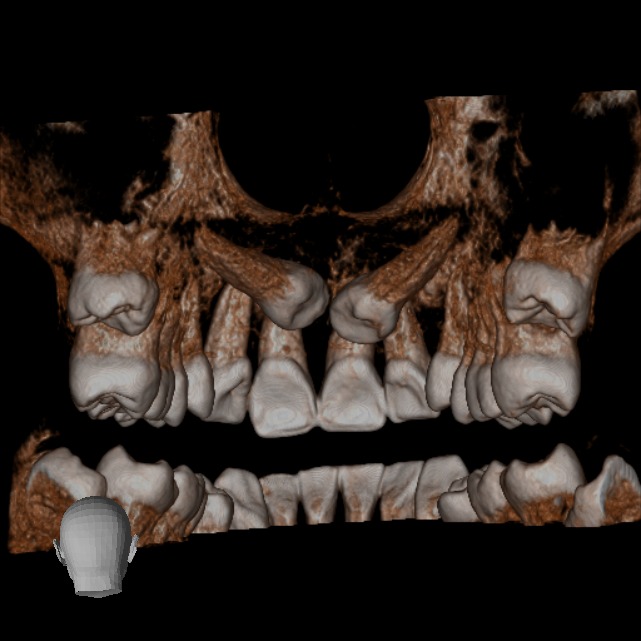

En nuestra clínica en Bogotá contamos con equipos de tomografía CBCT de última generación, que garantizan la más alta calidad en diagnóstico dental y permiten a tu odontólogo planificar cada detalle de tu tratamiento con máxima precisión.

• Rápido – Cómodo – Eficaz: Las imágenes obtenidas con nuestros equipos son altamente detalladas, mostrando los tejidos duros sin perder calidad.

Podemos analizar la posición y orientación de estructuras críticas como los nervios, las raíces dentales, los senos paranasales y la nariz, lo que ayuda a lograr un diagnóstico lo más preciso posible. Con nuestra tecnología de imagen avanzada, tu odontólogo podrá monitorear la estabilidad a largo plazo de tus restauraciones dentales, de esta forma se podrá obtener el resultado estético que deseas con tu tratamiento.